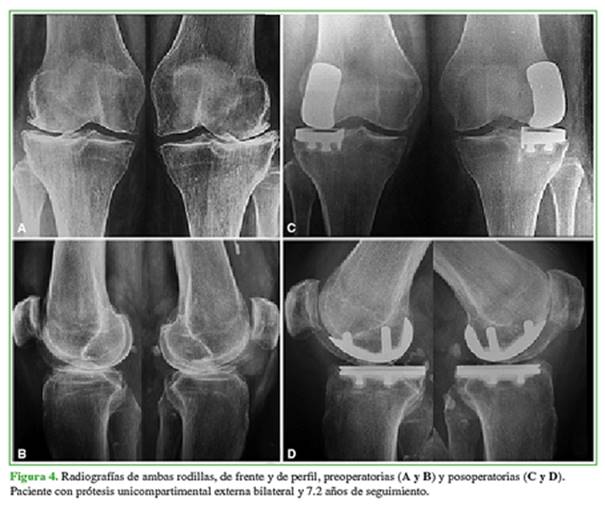

Antes de la cirugía, se tomaron radiografías de ambas rodillas, de frente y de perfil con carga bipodálica, axial de rótula a 30º de flexión (Merchant), de frente en semiflexión de 45º (Schuss), y radiografías en varo y valgo forzado para evaluar la suficiencia de los ligamentos colaterales, la corrección del deseje y el pinzamiento del compartimento contralateral. En el posoperatorio, se tomaron radiografías de frente, de perfil y axial de rótula (Figura 1).

Se midió el eje femorotibial pre- y posoperatorio con un goniómetro. Se cuantificó el grado de artrosis en el compartimento afectado según las clasificaciones de Ahlback para genu varo, y de Kellgren-Lawrence para genu valgo. Las evaluaciones estuvieron a cargo de uno de los autores que no participó en la cirugía.

En las radiografías, 81 rodillas presentaban genu varo artrósico, el 9,9% (n = 8) correspondía al grado 3 de la clasificación de Ahlback; el 43,2% (n = 35), al grado 4 y el 46,9% (n = 38), al grado 5. De estos últimos, 22 (57,9%) tenían subluxación en el plano coronal reductible en las radiografías con valgo forzado. En todos los casos de genu valgo artrósico, se constató un grado 4 de degeneración según la clasificación de Kellgren-Lawrence. El eje femo-rotibial preoperatorio fue de 9° ± 2,3° de varo para genu varo artrósico (rango 4-15) y de 14,6° ± 4,2° de valgo para genu valgo artrósico (rango 10-20). El eje femorotibial posoperatorio se corrigió a 3,6° ± 1,4° de varo (rango 1-9) y 7,4° ± 2,8° de valgo (rango 4-10), respectivamente (p <0,05) (Tabla 2, Figura 4).